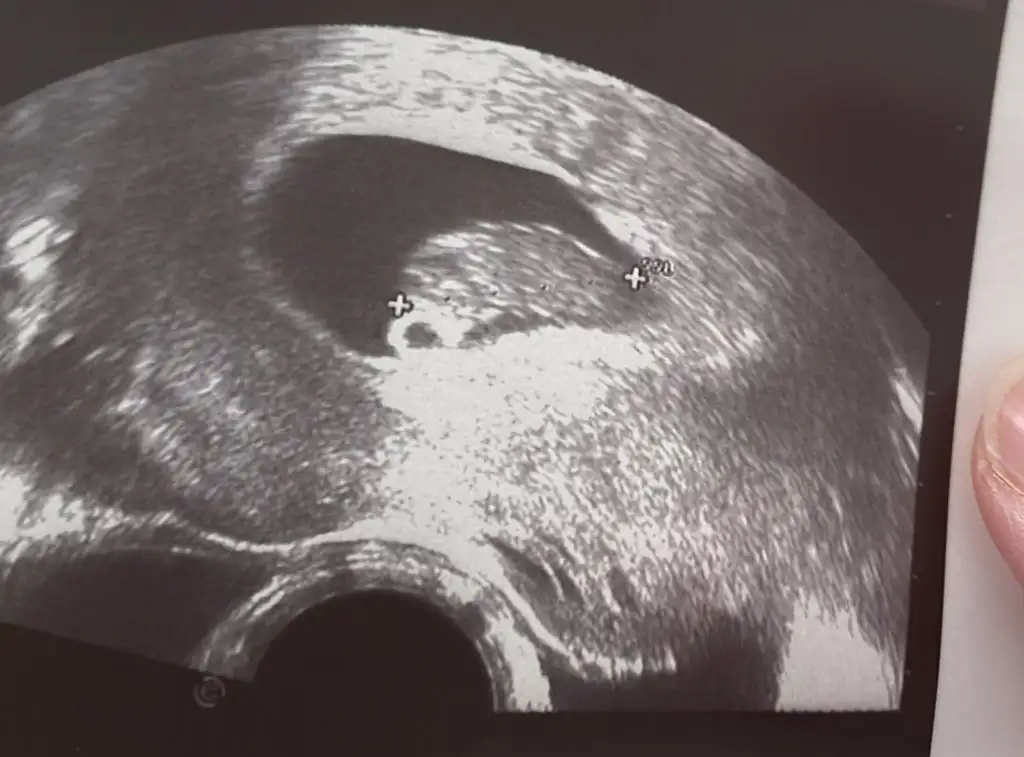

Bugün ki son resimlerimiz canım üçhagta sonra söyleyecekmiş doktorumuz